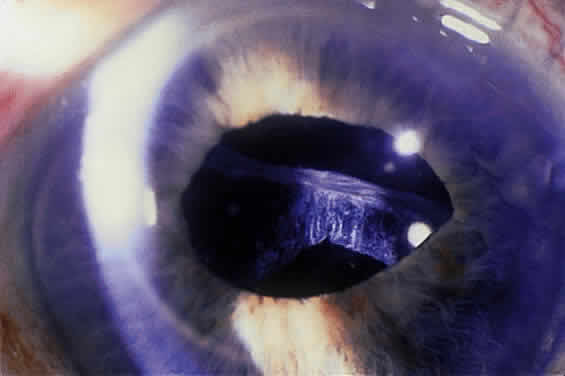

Deposition of exfoliative material on the anterior lens surface is the most commonly recognized feature of XFS and usually is best appreciated after pupillary dilation.43 A bull's-eye pattern generally is seen in which a translucent central zone and a granular peripheral zone of deposition are separated by an intermediate clear zone (Fig. 1). The translucent central zone of exfoliative material varies in diameter and may exhibit curled edges. In approximately 20% of patients with exfoliation, the central zone may be absent.38 The intermediate clear zone presumably results from lens contact with movement of the iris. The granular peripheral zone, which may be subtle but invariably is present in XFS, generally exhibits a well-delineated inner border and often shows numerous radial striations (Fig. 2). Occasionally, a bridge of exfoliative material may cross the clear zone to join the central zone and the granular peripheral zone.38,44